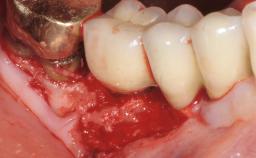

Surgical Treatment of Peri-Implantitis in the Posterior Mandible Associated with Hard- and Soft-Tissue Reconstruction

Paolo Casentini demonstrates that peri-implantitis can be successfully treated even at an advanced stage. He discusses a case in which the existing implants and prostheses were both retained while regenerating the defect and creating a band of keratinized tissue. A 69-year-old female patient was referred by her general dentist for evaluation of a recurrent infection at previously placed and restored implants in the posterior left mandible. The patient’s chief complaint was recurrent swelling and pain in the molar region of the left posterior mandible with discomfort during brushing in the same area. The patient reported receiving two implants (36 and 37) nine years earlier.